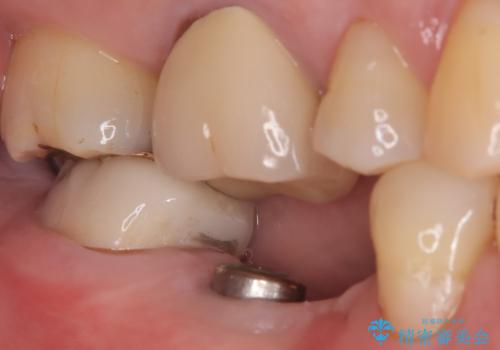

- 奥歯の欠損をインプラントで治療したいと来院された患者様です。

骨の状態が安定するまで待機したのち、インプラントを埋入しています。

スクリューリテインにて上部構造を連結しています。